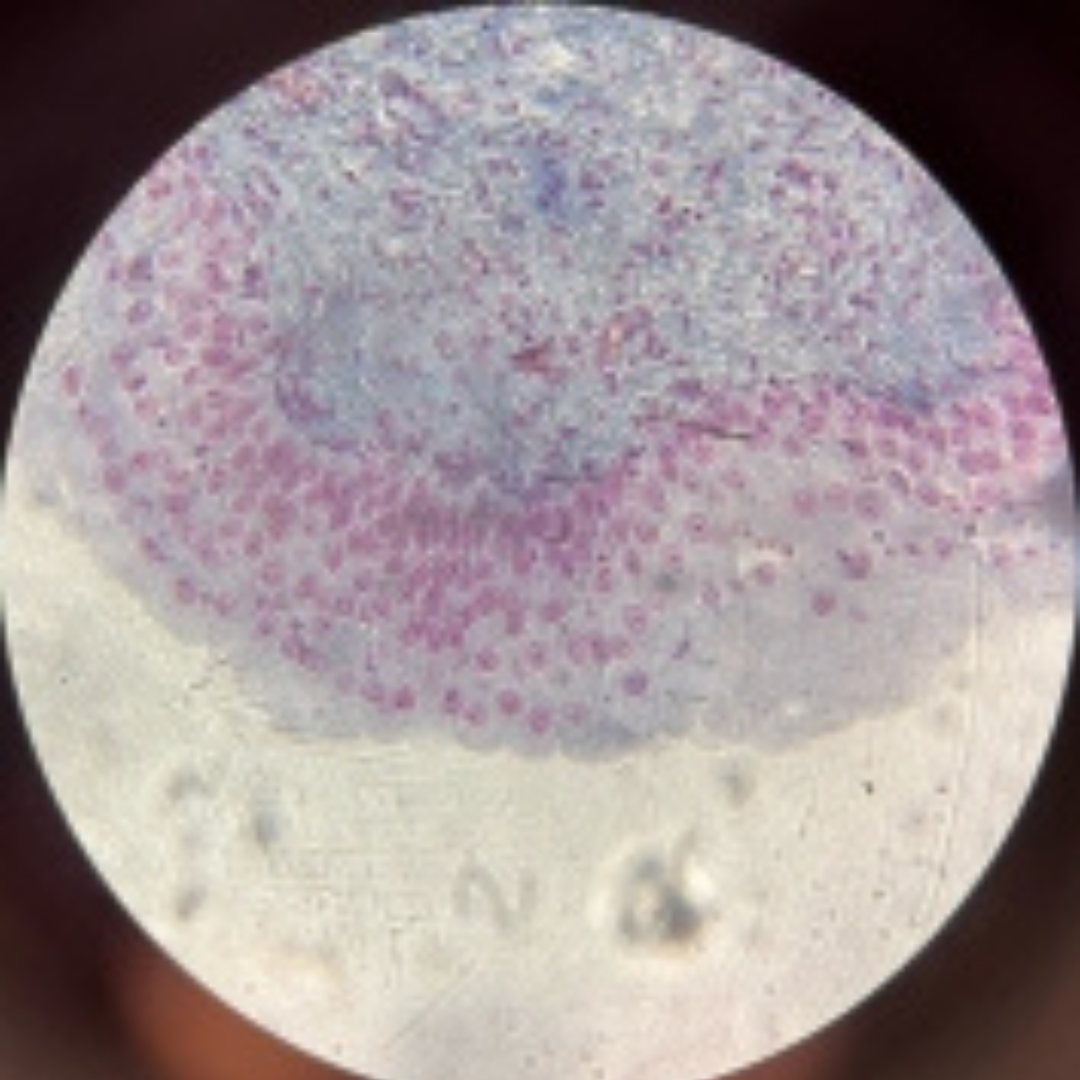

Reticular Connective Tissue (Lymph Node)